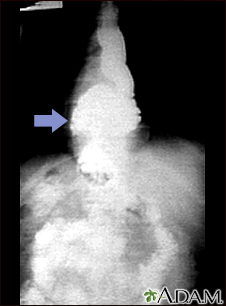

Radiografía de una hernia hiatal

Esta radiografía muestra una protrusión, a través del diafragma, de la porción superior del estómago (hernia hiatal).